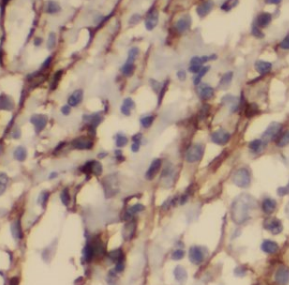

| 验证图片 | Immunohistochemistry of paraffin-embedded human colon cancer using FNab04305(KPNB1 antibody) at dilution of 1:50 mouse brain tissue were subjected to SDS PAGE followed by western blot with FNab04305(KPNB1 Antibody) at dilution of 1:600 |